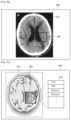

- the first image is an MRI image of a head of a patient.

- the UI unit 530 When a first region in the first image is selected, the UI unit 530 outputs a first list including at least one protocol applied while scanning the object, and receives a selection on a first protocol included in the first list.

- the first list output by the UI unit 530 is displayed through the display unit 520.

- the control unit 510 may control a second image reconstructed by using image data obtained by applying the first protocol to be overlaid and displayed on the first region of the first image.